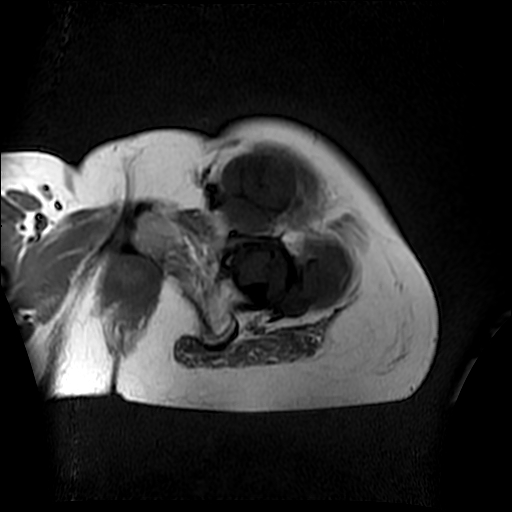

左侧大腿外伤10余年,当时情况不清,发现左侧大腿肿胀7年余,而后又有多次外伤史,近1年来出现疼痛,减重半年。查体:左侧大腿肿胀明显,皮温、肤色正常。

增强

软组织肿块,股骨破坏,增强不均匀强化-----支持恶性肿瘤